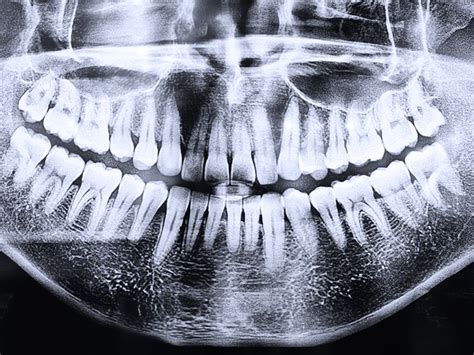

La radiografía panorámica, también conocida como ortopantomografía, es la prueba radiológica más común en la consulta dental y se realiza al paciente cuando acude por primera vez a la clínica. A pesar de ser habitual, existe desconocimiento sobre su uso.

Esta técnica radiológica representa en una única película una imagen general de la boca y es fundamental para el diagnóstico odontológico de dientes, maxilar y mandíbula. Se trata de una proyección radiográfica lateral paralela al plano medio del cráneo y cuello.

La ortopantomografía es una técnica radiológica utilizada en odontología, especialmente en ortodoncia, que permite obtener una imagen panorámica completa de los dientes, mandíbula y maxilar. Se realiza mediante un equipo especial llamado ortopantomógrafo, el cual puede ser convencional o digital. Este equipo es esencial para el diagnóstico en la clínica dental, y es ampliamente utilizado en cirugía oral, implantología, ortodoncia, periodoncia y patología oral.

- Dientes: La dentición debe mostrar una curva suave en la línea de sonrisa, con un espacio fácil de distinguir entre los dientes superiores e inferiores. Los dientes posteriores deben tener un tamaño normal y no debe existir una superposición excesiva entre los premolares. Los ápices de los dientes anteriores deben estar completos y las coronas deben ser visibles en la imagen radiográfica.

- Senos y nariz: Los tejidos blandos de la nariz y sus cartílagos deben estar claramente visibles en la imagen radiográfica. La sombra del paladar duro debe ser notoria y algunas imágenes fantasmas del paladar pueden ser visibles en los senos maxilares. En la imagen la lengua se debe observar en contacto con el paladar.

- Cóndilos mandibulares: Ambos cóndilos deben aparecer centrados en la imagen radiográfica, con tamaño y altura similares en relación al plano horizontal.

- Rama de la mandíbula y columna cervical: La rama mandibular debe ser similar en ambos lados de la imagen. La columna vertebral, cuando sea visible, no debe estar superpuesta a la rama mandibular y la distancia entre ellas debe ser igual en ambos lados.

- Cuerpo mandibular: La corteza inferior de la mandíbula debe mostrar una imagen uniforme y continua. No deben existir imágenes fantasmas o dobles imágenes del hueso hioides y la línea media de la mandíbula y maxilar no deben estar aumentadas.